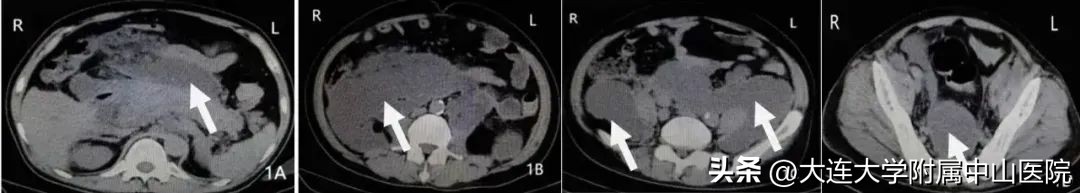

入院腹部CT检查:胰腺肿大,腹膜后广泛感染坏死组织及脓液。

复查腹部CT提示原腹膜后感染坏死组织及脓液消失